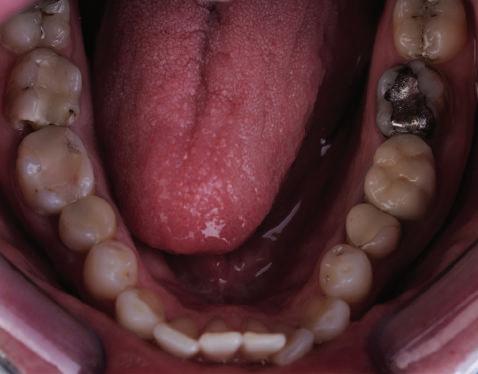

Пациент: 30 г., мъж Първо посещение: 02.08.2018 г. Основни оплаквания: Лицева болка, главо болие и болка в дясната темпоромандибу ларна става, естетични съображения РАБОТЕН ПРОТОКОЛ:

диагностика терапия със сплинт ортодонтска рехабилитация диагностична реоценка вертикален размер на оклузията –диагностичен восъчен моделаж протетична рехабилитация работа в зъботехническата лабора тория диагностична реоценка поддръжка

СПИСЪК С ПРОБЛЕМИ:

тясна зъбна дъга – горна и долна струпване във фронта – в горна и долна челюст вертикален излишък в максилата, водещ до скелетна гингивална усмивка недобри амалгамени и композитни обтурации наличие на мъдреци 18, 38, 48 – стръм на

установяване на клас I функционално водене с канинова защита елиминиране на дисталните блокажи

ЛЕЧЕБЕН ПЛАН: екстракция на мъдреците възстановяване на компрометирани те зъби и ендодонтски релечения терапия със сплинт гингивектомия в горна челюст ортодонтско лечение: – нивелиране и подреждане на зъбите в горна и долна челюст;

– интрузия на цялата горна зъбна дъга; – дъга Gummetal с tip-back извивки в до лна челюст за нивелиране на крива та на Шпее; – ретенция. VTO – диагностичен восъчен моделаж след финалната кондилография: проме ни в оклузалната равнина; промени в относителния кондиларен наклон протетична рехабилитация

Пациентът постъпи в моята клини ка с наличие на темпоромандибуларен дисфункционален болков синдром, едно странно изместен диск с редукция в дяс ната става, клас II, подклас 2, тесни гор на и долна челюст със струпване, дъл бок овърбайт

орални снимки и снимки на позата, пал пация на мускулите, брукс-чекър, оклу зограми, кондилография, рентгеногра фии, СВСТ и ядрено-магнитен резонанс на темпоромандибуларните стави). Преди началото на ортодонтското лечение всички стари възстановява ния бяха свалени и бяха заменени с дъл госрочни временни от хибридна керами ка. На девитализираните зъби бе прове дено ендодонтско релечение. Индивиду ализиран оклузален сплинт бе направен с цел да се постигне контролирано репо зициониране на долната челюст, като носенето му продължи три месеца до възстановяване на правилната позиция на ставния диск и затихване на орофаци алната болка и дискомфорт в ставата. Брекетите в горната челюст бяха за лепени, за да започне подреждането и нивелирането на зъбите, докато паци ентът все още носеше сплинта. След края на терапията със сплинта бе на правена кондилография, за да се потвър ди триизмерната позиция на долната челюст. След залепване на брекетите в долна

тация на долната челюст. Дъга GUMMETAL с tip-back извивки бе поставена в долната челюст за ниве лиране кривата на Шпее. Случаят бе финализиран с 19x25 SS дъги в горната и долната зъбна дъга за координиране. Преди да се изготви финалният восъ чен моделаж, естетичните и лицеви те характеристики бяха анализирани с помощта на дигитален дизайн на ус мивката, за да се създаде мок-ъп, чии то форма и размери да бъдат одобрени от пациента. Бе оценена фонетиката и бяха заснети лицеви снимки и видеа. Зъ бите бяха изпилени, като препарация та бе изцяло водена от функционалния восъчен моделаж, прехвърлен в устата на пациента. След препарацията восъч ният моделаж бе напаснат и насложен върху препарационния модел и бе фрезо ван от e-max multi bl 1. Циментирането на финалните конструкции бе направе но при изолация с кофердам, следвайки адхезивния протокол. След циментирането бе направено проследяване на оклузията чрез снема не на отпечатъци, монтиране на моде лите в артикулатор в окончателната интеркуспидация и внимателно прове ряване за наличие на блокажи при воде ни движения.

В конкретния случай комбинирах златния стандарт при статична по зиция с динамична оценка на функци ята на темпоромандибуларната ста ва, за да диагностицирам и лекувам ней ната дисфункция.

Д-р Манол Ивчев, България, зт. Leandro Gambogi, Бразилия

6 Dental Tribune Bulgarian Edition / октомври 2022 г. КРАТКО ОПИСАНИЕ НА КЛИНИЧНИЯ СЛУЧАЙ

оклузална равнина ендодонтски проблеми – 15, 25, 35, 36, 37, 45, 46, 47 отклонение на срединната линия с 2 мм вляво в долна челюст мускулни болки ДИАГНОСТИКА: скелетен клас II зъбен клас II функция: ограничения в движенията –мускулни проблеми; хлабави лигамен ти – латеротрузивни странични про блеми при медиотрузия вдясно; девиа ция на долната челюст вляво. ЦЕЛИ НА ЛЕЧЕНИЕТО: разширяване на горната и долната зъбна дъга промяна на оклузалната равнина в по сока надолу – намаляване на наклона на оклузалната равнина, така че да стане по-плоска, и постигане на пра вилна оклузална равнина дистално намаляване на вертикалния размер на оклузията (LFH)

и гингивална усмивка. Започнахме лечението с пълна диагно стика (анамнеза, интраорални, екстра

та челюст 4 минивинта (TADs) бяха по ставени в максилата – 2 в небцето и 2 интрарадикуларно във фронта, с цел да се извърши интрузия на цялата зъбна дъга, да се коригира гингивалната усмивка и да се позволи провеждането на обратна на часовниковата стрелка авторо

След стабилизира не на ставите и долната челюст в те рапевтична позиция постигнах орто донтски премествания и скелетни ко рекции, които обикновено са възмож ни единствено посредством ортогнат на хирургия. Преминах от аналогов мо дел на работа към изцяло дигитален, за да се хармонизира лицевата естетика чрез Digital Smile Design, като същевре менно обаче изработих функционален аналогов восъчен моделаж и на двете че люсти, за да мога да приложа оклузална та концепция на Славичек. След което напаснах препарациите с аналоговия во съчен моделаж при изцяло дигитални ус ловия с цел фрезоване на короните. Всич ки тези комбинации правят случая из ключително комплексен. В крайна сметка този сложен случай бе лекуван с най-добрата възможна ком бинация от възможности, които ана логовият и дигиталният свят предла гат, за да се постигне красота, която е следствие от отлична функция. ОКЛУЗАЛЕН „БАЛЕТ“ С РОЗОВАТА ЕСТЕТИКА Клиничен случай, победител в категория „Комплексно естетично възстановяване“ в конкурса „Усмивка на годината 2022“ Преди След

7Dental Tribune Bulgarian Edition / октомври 2022 г. Преди лечението Фиг. 1 Фиг. 4 Фиг. 7 Фиг. 10 Фиг. 13 Фиг. 16 Фиг. 17 Фиг. 18 Фиг. 19 Фиг. 20 Фиг. 11 Фиг. 14 Фиг. 12 Фиг. 15 Фиг. 8 Фиг. 9 Фиг. 5 Фиг. 6 Фиг. 2 Фиг. 3

8 Dental Tribune Bulgarian Edition / октомври 2022 г. По време на лечението Фиг. 21 Фиг. 25 Фиг. 30 Фиг. 31 Фиг. 34 Фиг. 38 Фиг. 40 Фиг. 44 Фиг. 48 Фиг. 50 Фиг. 49 Фиг. 46 Фиг. 39 Фиг. 41 Фиг. 45 Фиг. 47 Фиг. 42 Фиг. 43 Фиг. 35 Фиг. 36 Фиг. 37 Фиг. 32 Фиг. 33 Фиг. 26 Фиг. 28 Фиг. 29 Фиг. 27 Фиг. 22 Фиг. 23 Фиг. 24

9Dental Tribune Bulgarian Edition / октомври 2022 г. След лечението За авторите: Д-р Манол Ивчев е създател на COLDY DENT Functional Atelier, завършва дентална медицина във ФДМ, София. Шест години е стажант в ортодонтска практика. Интересите му са изцяло насочени към функционалната дентална медицина. Посещава курсовете на Доусън и Льо Гал. Преминава редица обучения, акредитирани от Института на Славичек във Виена – VieSID. Впоследствие става най-младият инструктор във VieSID. Придобива права да преподава философията на проф. Рудолф Славичек в България. В практиката си се придържа към протоколите на Славичек за функционално лече ние и диагностика, тъй като те са насочени към комплексно лечение. Завършва всички нива за морфология на зъбите и моделаж при Janos Mako. Повишава знанията си по функционална ортодонтия чрез индивидуален курс в Румъния. Д-р Ивчев е и сертифициран зъболекар по лингвална ортодонтия от Катедрата по ортодонтия от Университета по стоматология в Тегу, Южна Корея. Сертифициран е и за лечение на ортодонтски аномалии чрез миофункционални апарати, а също и за ортодонтия, подпомагана от миниимпланти, отново от Университета по стоматология в Южна Корея. Завършва индивидуално обучение по функционална ортодонтия в Университета по дентална медицина в Богота, Колумбия, както и индивидуално обучение по функционална ортодонтия и физиотерапия по про токола на Mariano Rocabado. Има завършено индивидуално обучение по функционална зъботехника и функционален Wax-Up клас I,II и III. Завършва курс за Digital Smile Design и Skin Concept в Люксембург при Christian Coachman, Florin Cofar, Paulo Kano, Josef Kunkela, Livio Yoshinagа. Зт. Leandro Gambogi, Бразилия, завършва зъботехника през 1999 г. Експерт и пионер в дигиталната диагностика. Лектор и инструктор на курсове в областта на дигиталното протезиране. Понастоящем е главен изпълнителен директор и зъботехник в DENTALE DIGITAL LAB. В периода януари 2005 г. – декември 2006 г. завършва бизнес управление и администрация в Methodist University Center Izabela Hendrix. Съавтор на книгата Odontologia Digital: Desafiando os Limites, глава 5: „Дигитално включване във времето. Технология CAD/CAM“. Преминал множество обучения при световноизвестни кли ницисти. Фиг. 51 Фиг. 54 Фиг. 57 Фиг. 58 Фиг. 63 Фиг. 64 Фиг. 65 Фиг. 59 Фиг. 61 Фиг. 62 Фиг. 60 Фиг. 55 Фиг. 56 Фиг. 52 Фиг. 53 Фиг. 66